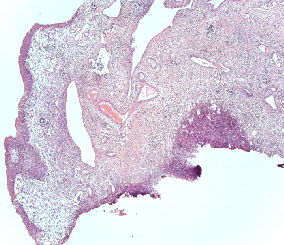

Патоморфологическая картина продемонстрирована на рисунке ниже.

Патоморфологическое исследование пациентка О.

Морфологическая картина полипоидного цистита с наличием гиперплазированного уротелия, признаков острого и хронического воспаления, реактивной уротелиальной атипии с множественными митозами, отеком собственной пластинки слизистой с фиброзом и полнокровными сосудами и полипоидными выпячиваниями. Окраска гематоксилин-эозином, х5